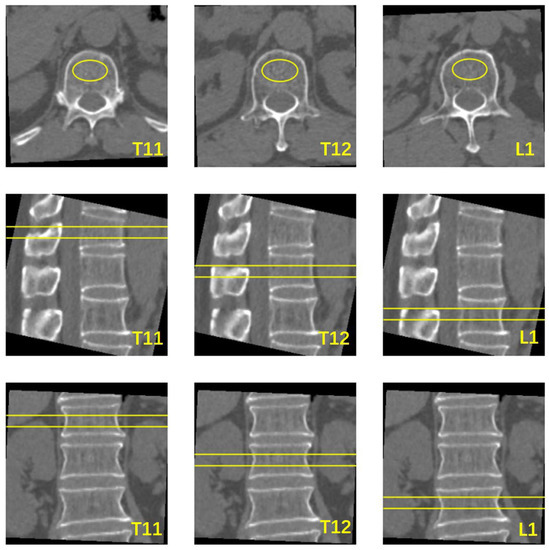

2.3. Image Reconstruction and Quantitative Data Measurement